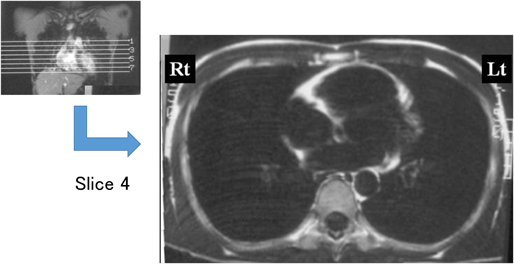

小児では先天性心疾患や心臓手術後,心筋症(肥大型心筋症,拡張型心筋症,拘束型心筋症,左室緻密化障害,不整脈原性右室心筋症)で不整脈の合併がみられる.成人では心筋虚血・サルコイドーシスなどの頻度が多い.心筋症の中でもとくに肥大型心筋症は若年者の運動中の失神や突然死の原因として注意すべき疾患である.初期は無症状で心電図変化が先行することが多い.心エコーで心室壁肥厚などの変化があっても,初期の軽度心室拡張障害では自覚症状に乏しい.12誘導心電図では左室肥大,異常Q波,ST-T変化などを呈するが,その組み合わせは様々である.Fig. 9は深いQ波を呈した肥大型心筋症の例で,Fig. 10はST-T変化が主体の肥大型心筋症の例である.運動時の失神・突然死の機序としては,心室性不整脈(特に心室細動)が原因と言われている.また不整脈原性右室心筋症は,小児例は少ないが若年者にみられる心室性不整脈とそれに伴う症状が主体の心筋症である.Fig. 11は15歳時に学校検診で心電図異常を指摘され,経過中に持続性心室頻拍を頻回に呈した症例である.安静時の洞性脈時にはV1でε波を認め,その後持続性心室頻拍が始まっている.MRIでは右室心筋の脂肪変性を広範に認めた(Fig. 12).

Pediatric Cardiology and Cardiac Surgery 33(2): 111-119 (2017)

Fig. 12 Cardiac MRI of ARVC revealing fatty infiltration of the right ventricular myocardium and dilatation of the right ventricle

Same case as in Fig. 9.